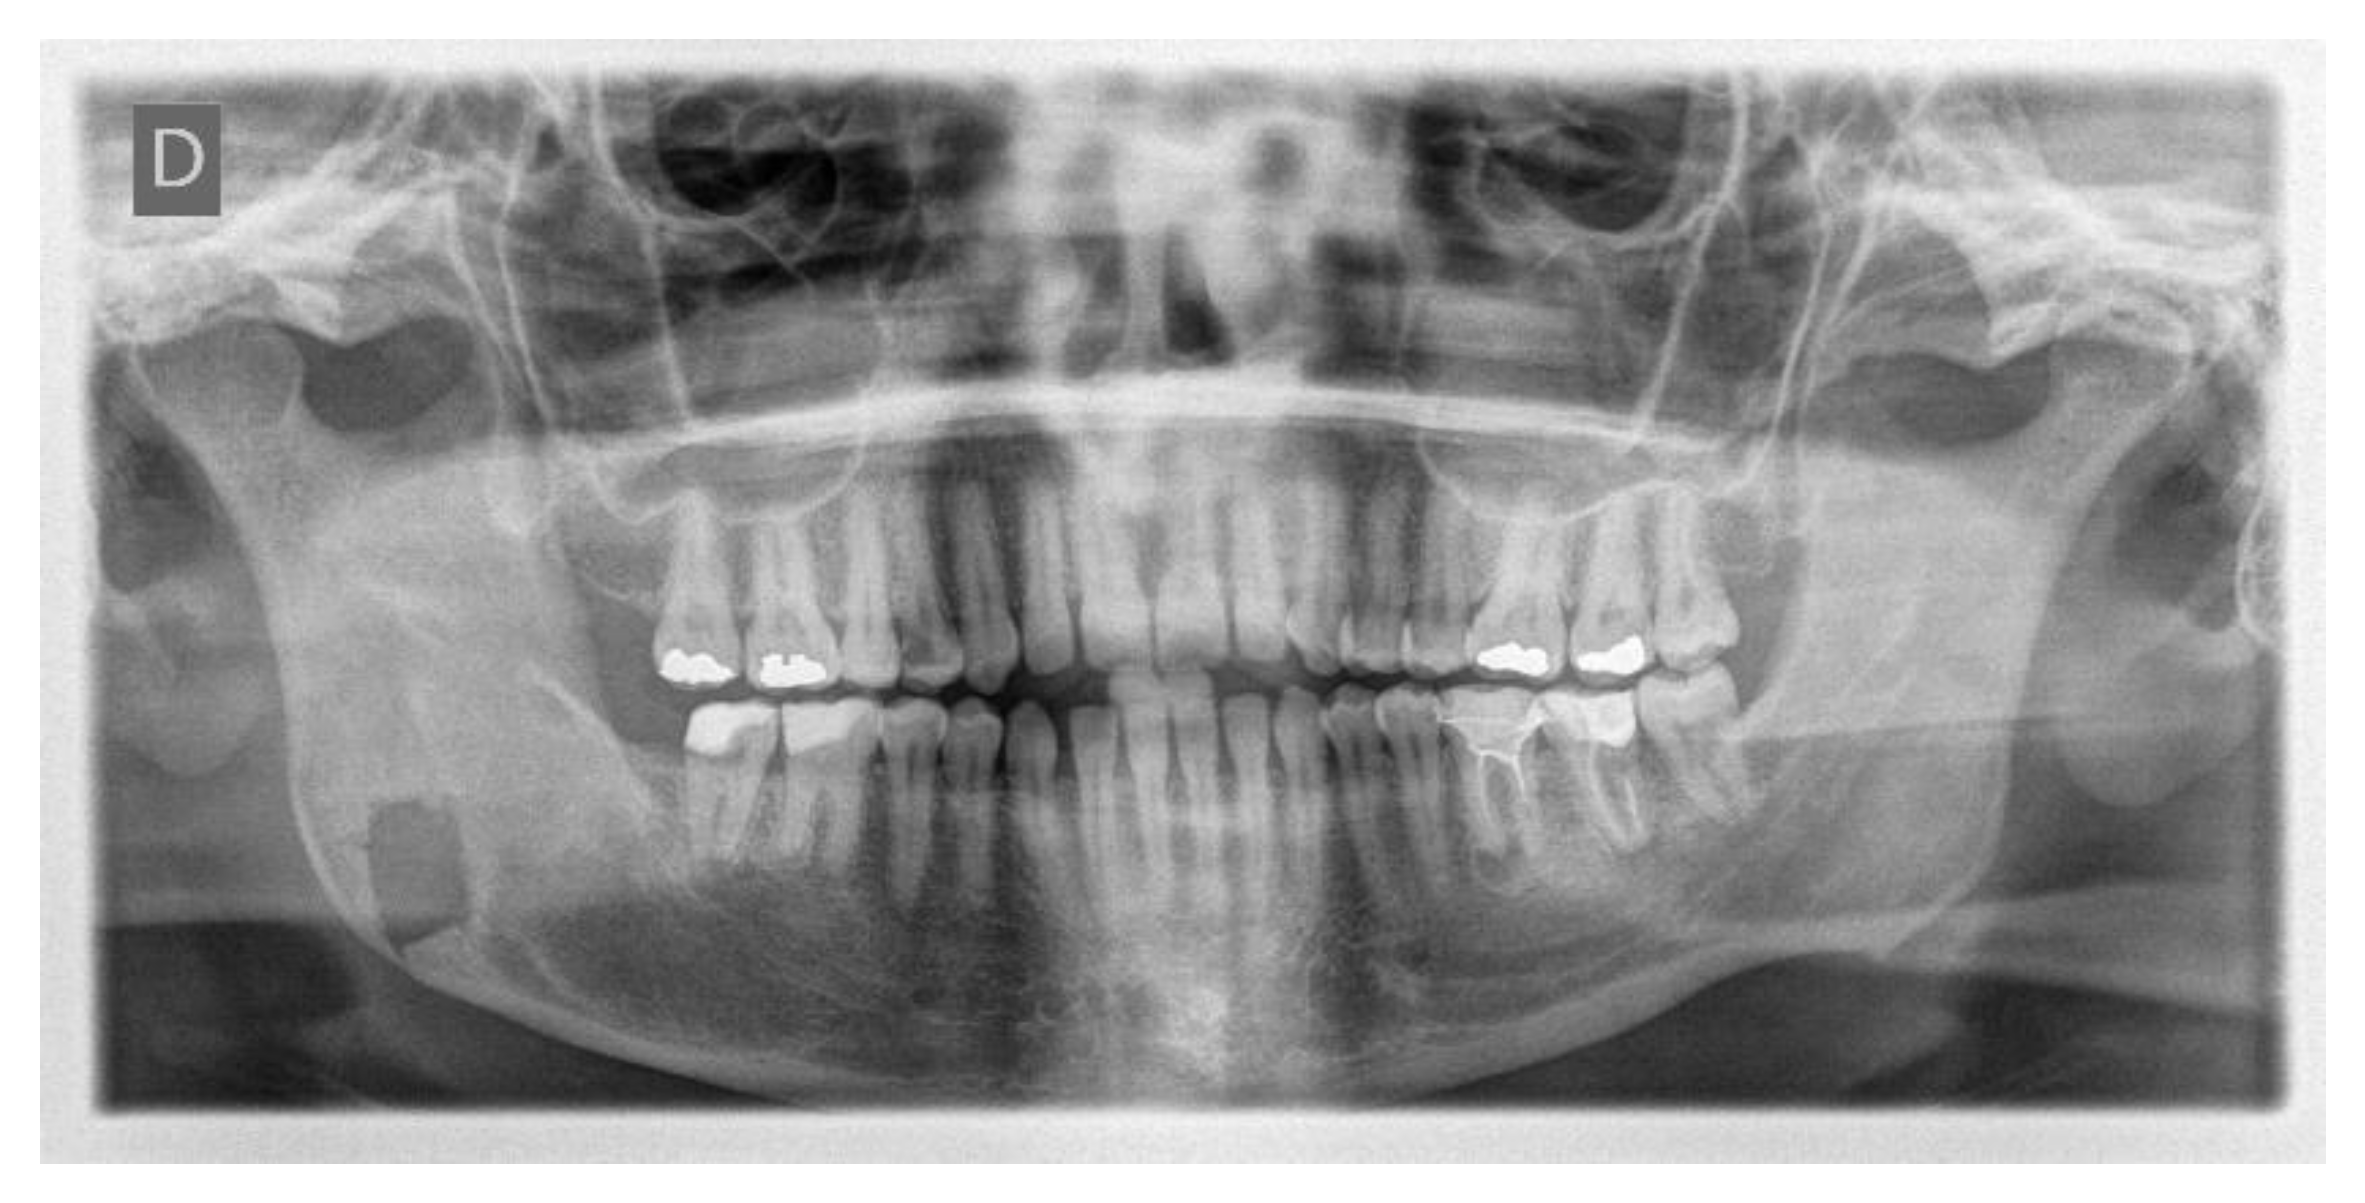

The day following the surgery, a follow-up OPT X-ray was requested, which displayed the resection area and the integrity of the lower and upper borders of the mandible, in accordance with the preoperative virtual planning (Figure 15).

Figure 15.

Postoperative OPT X-ray showing the resection area and the integrity of the lower and upper borders of the mandible.

The histological examination of the surgical resection confirmed the diagnosis of a recurrent unicystic ameloblastoma.

To date, the patient undergoes annual consultations in our department with OPT X-rays, with a follow-up duration of 9 years, and no new recurrence has been detected.